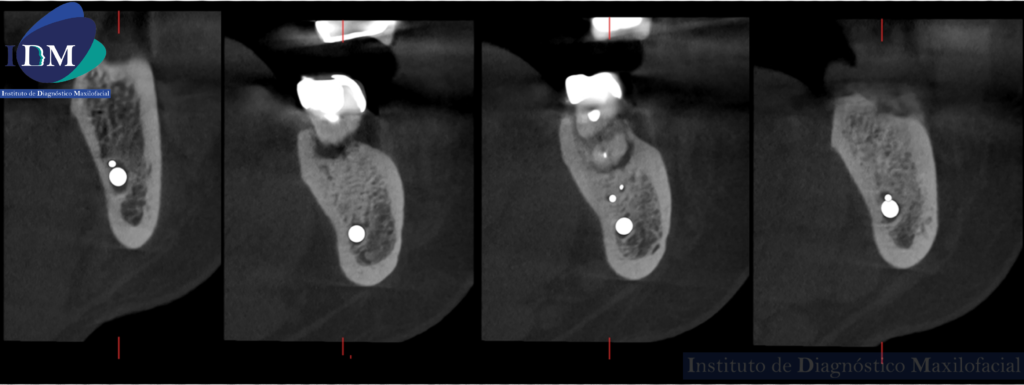

CORTES CORONALES

Así mismo se evidencia en la tomografía localizada una variante anatómica por parte del conducto dentario inferior. Donde se visualizada dos ramos accesorios del tronco principal sin confluencia.